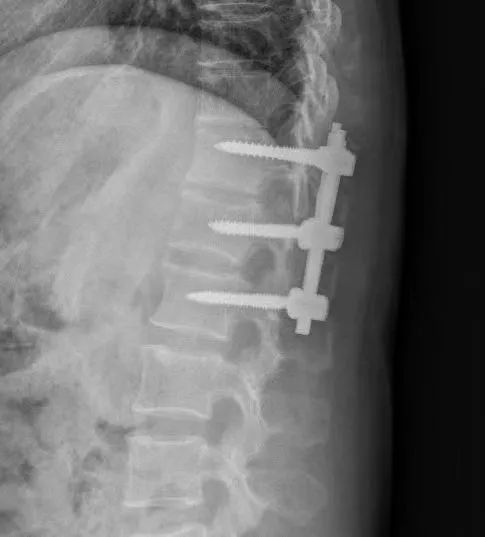

脊柱病區(qū)主治醫(yī)師張聰表示,劉師傅胸12椎體為爆裂性骨折,變形嚴(yán)重,如果采取保守治療,可能會(huì)出現(xiàn)骨折畸形愈合、延遲愈合或不愈合的問題,另外就是長期臥床容易導(dǎo)致肌肉萎縮、肺炎、壓瘡、深靜脈血栓等并發(fā)癥,嚴(yán)重者可危及生命。

經(jīng)過綜合考慮,他建議劉師傅進(jìn)行切開復(fù)位椎弓根釘內(nèi)固定手術(shù)治療,通過內(nèi)固定裝置恢復(fù)受傷椎體的高度與脊柱的正常曲度,從而維持脊柱的穩(wěn)定性。術(shù)后早期就能下地行走,也避免了一系列并發(fā)癥的發(fā)生。劉師傅接受了手術(shù)治療的方案。

手術(shù)很順利,術(shù)后第二天,劉師傅便可以適當(dāng)坐立活動(dòng),目前他也在進(jìn)一步康復(fù)中。